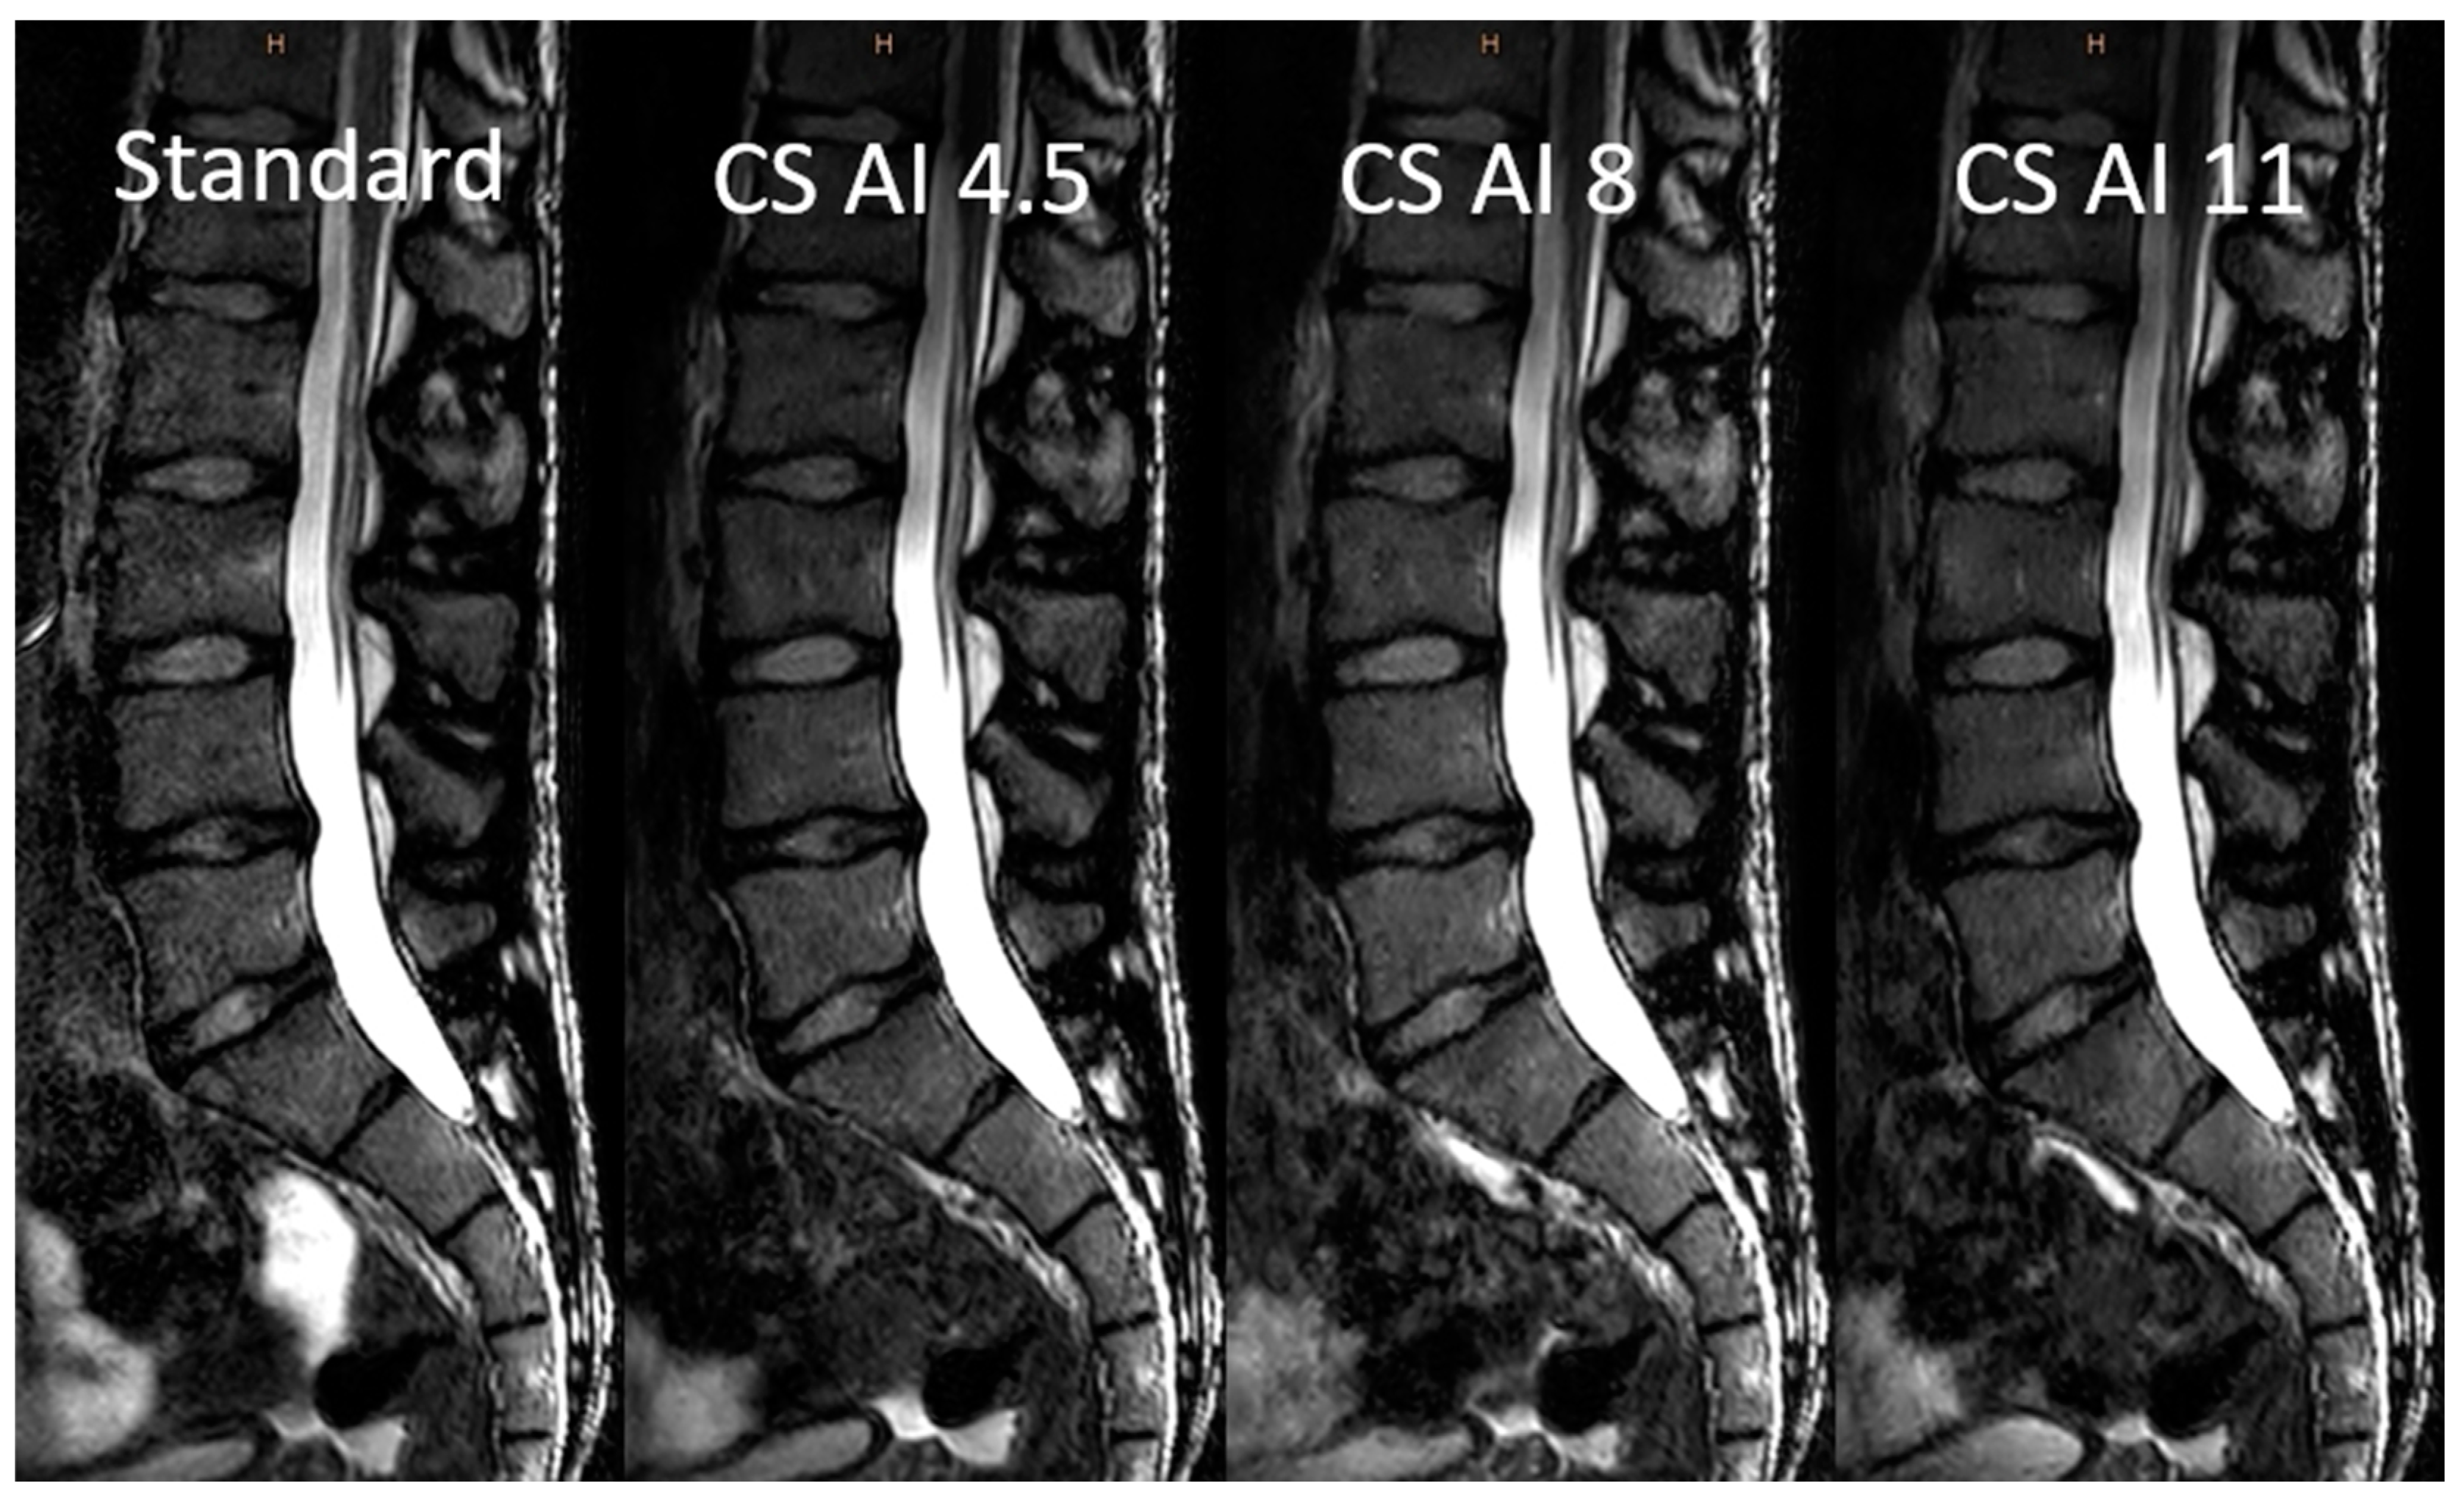

3.2. Image Analysis

3.3. Objective Image Analysis

3.4. Subjective Image Analysis